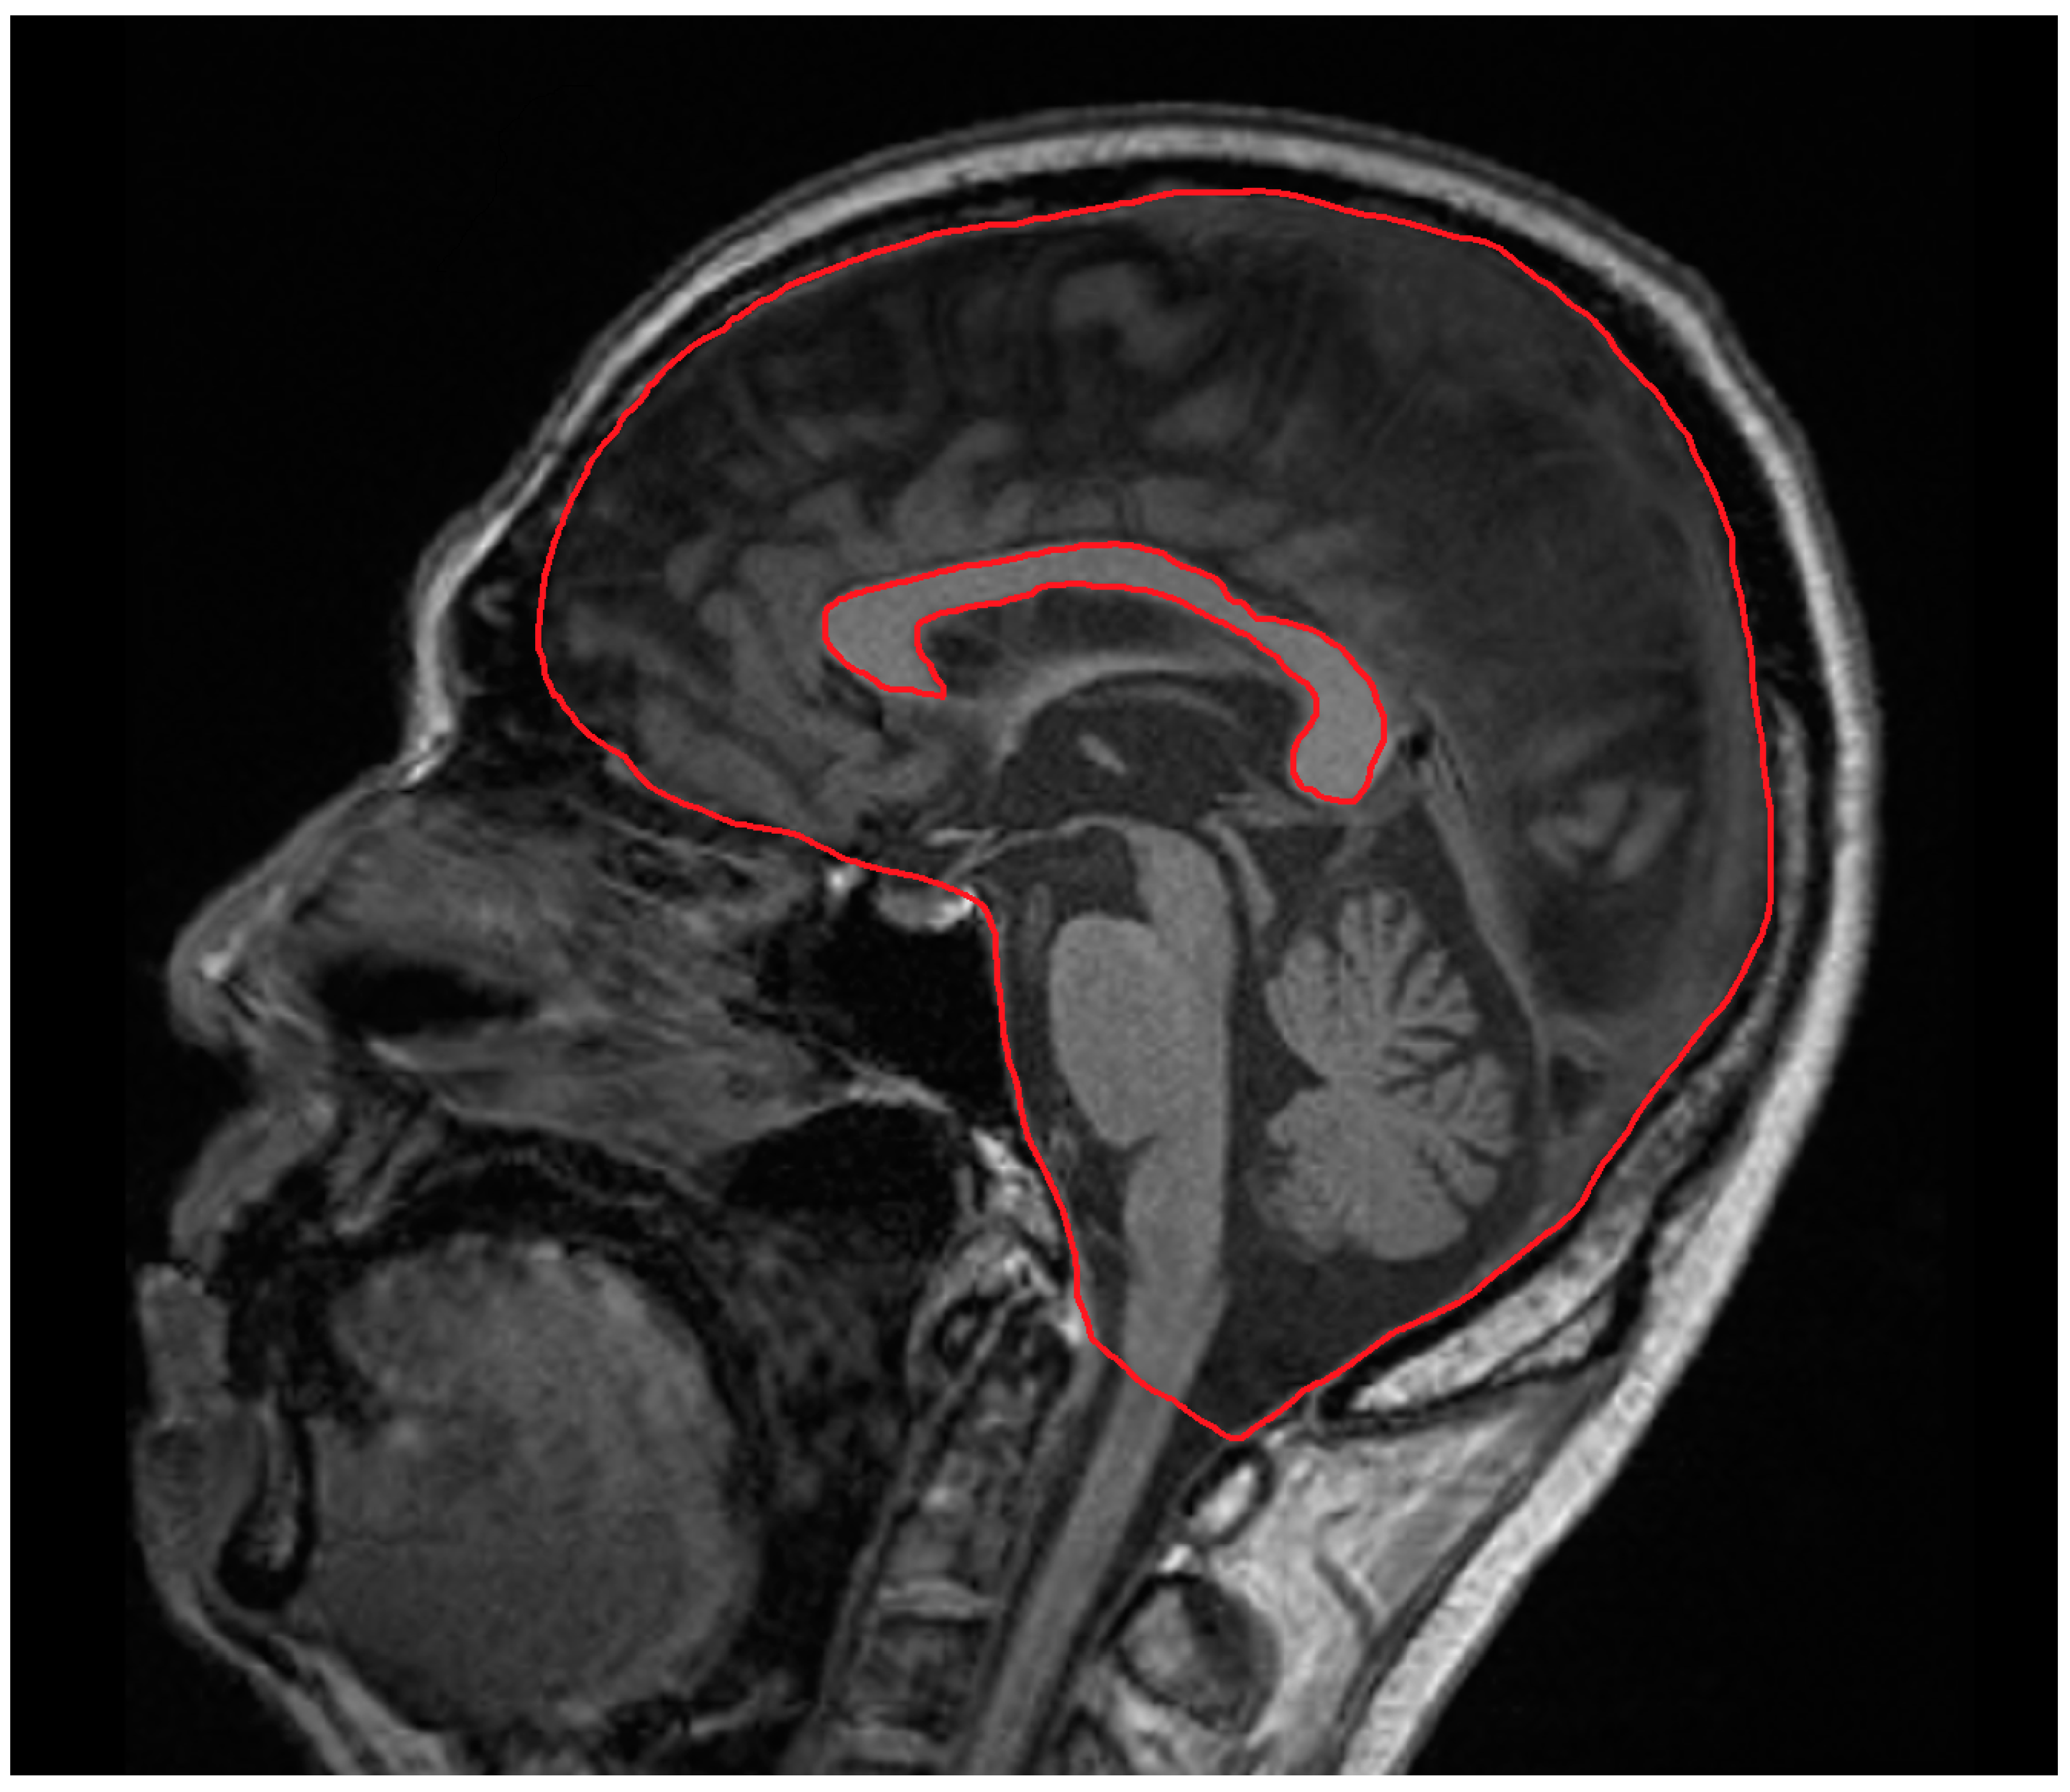

CCA was manually measured on a sagittal midline T1-weighted sequence using a picture archiving and communication system (PACS) by a neurologist (SA). The intracranial skull surface area was manually measured on the same image (Figure 1). The CCA was normalized to the intracranial skull surface area to account for head size. To assess intrarater reliability for normalized CCA (nCCA), we calculated the intraclass correlation coefficient based on ratings obtained during a second session three months later. Interrater reliability for nCCA was evaluated by comparing the ratings of other authors (TO and RK). All MRI assessments were randomized, with examiners blinded to the clinical assessments and ratings of the other examiners.

Figure 1.

Techniques for manually measuring the corpus callosum area and intracranial skull surface area on midline T1-weighted magnetic resonance imaging sequence.